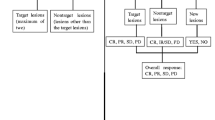

For each lesion, the two readers were asked to report size, depth (starting from the skin surface and ending to the deeper aspect of the lesion) and segment location according to Couinaud classification system. The two readers were also asked to report (1) complete response (CR): the absence of any nodular arterially enhancing portion within or at the margin of treated HCC; (2) residual tumor (RT): any nodular arterially enhancing area within or along the margin of the treated HCC [6, 10]. Residual viable tumor was also categorized as (1) ingrowth pattern, when a hypervascular focus was detected within the edge of a treated nodule and (2) outgrowth pattern, when a hypervascular focus was detected around a necrotic treated nodule and in continuity with its border [11]. The presence of a uniform and thin (4–5 to 7–8-mm thick) peripheral rim of contrast enhancement surrounding the treated zone was regarded as benign reactive hyperemia [6]. The time needed for a complete evaluation of each single 3D volumetric dataset, including defining and zooming the area of interest, choosing the appropriate depth, number, and spacing of slices was also measured.

The influence of both methods on clinical outcome was evaluated on a three-point scale: (1) 2D CEUS imaging changed diagnosis and consequently lesion’s management (score 1); 3D CEUS and 2D CEUS studies provided the same diagnosis (score 2); 3D CEUS imaging changed diagnosis and consequently lesion’s management (score 3).